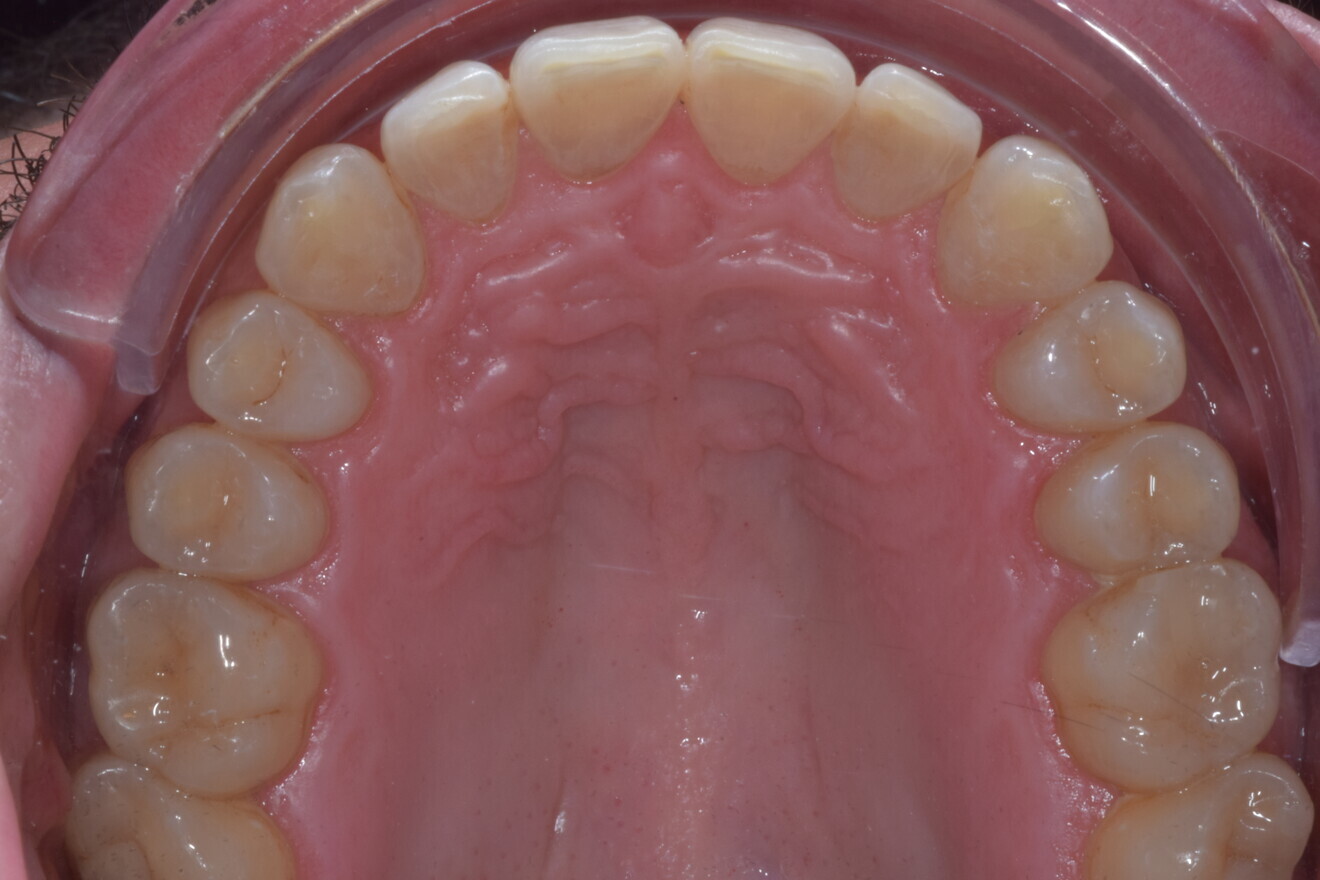

A 37-year-old male patient presented with the chief need for re establishing anterior alignment in both arches. Facial analysis showed a short face with a flat profile but proper chin projection (Figs. 9–12), and clinical examination revealed a skeletal Class I (ANB = 0.89°) and dental Class I malocclusion with severe deep bite (almost 100%), a deep curve of Spee, normal maxillary central incisor torque (Ui–FH = 110°), mild maxillary crowding and moderate mandibular crowding (Figs. 13–18). The deep bite components were represented in this patient by the severe skeletal condition of hypo divergent pattern (FMA = 14.24°) with normal maxillary and mandibular incisor inclination and decreased gonial angle (110.46°). Analysis of the cephalometric radiograph indicated a reduced lower anterior facial height, combined with a hypo-divergent pattern (Fig. 19). The only treatment option suggested was orthodontic treatment with aligners for deep bite correction with all the features described (bite ramps, pressure area, 3D curve of Spee levelling, Class II elastics and heavy occlusal contacts).

Fig. 13

Fig. 14

Fig. 15

Fig. 16

Fig. 17

Fig. 18